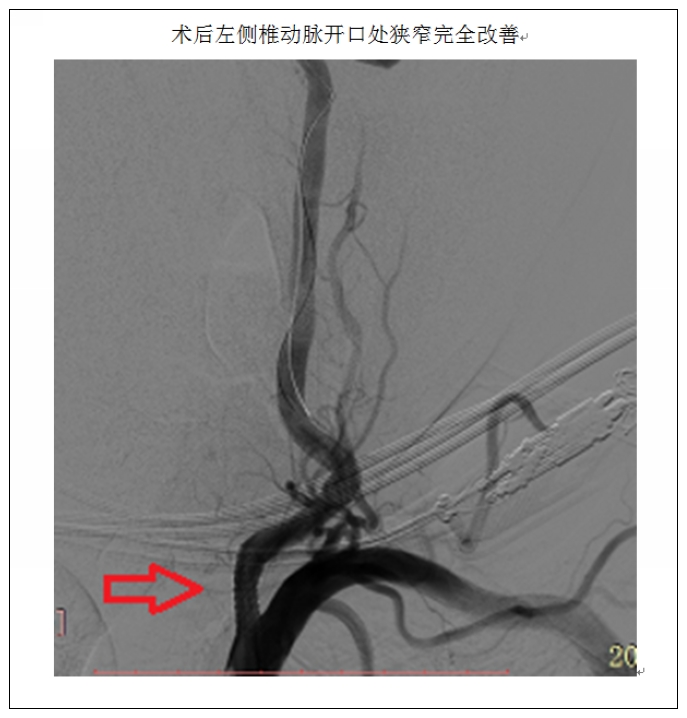

患者66岁,既往有高血压病及糖尿病病史多年,今年3月因“突发意识障碍2小时”在我院脑外科行急诊取栓术,术中造影提示基底动脉及左侧椎动脉重度狭窄。术后患者恢复良好,考虑到患者基底动脉重度狭窄系此次急性脑梗死责任病灶,短期内再发致命性脑干梗死的风险很大,后转入我科行二期介入治疗。患者基底动脉狭窄处穿支血管丰富,对介入治疗技术要求高、风险大、易并发致命性脑干出血或穿支闭塞致脑干梗死;患者的基底动脉及左侧椎动脉开口串联病变,横跨颅内外;左侧椎动脉开口处重度狭窄并迂曲,系手术途径,必须同期治疗。经过充分的术前准备后, 4月3日,患者在全麻下行基底动脉+左侧椎动脉联合支架成形术,术中提示左侧椎动脉70%狭窄,基底动脉远端90%狭窄。经过三个多小时的共同努力,治疗团队于基底动脉及左侧椎动脉开口处各置入一枚支架,术后血管形态及血流通畅程度较术前明显改善。患者现已痊愈出院,住院观察期间无并发症发生。